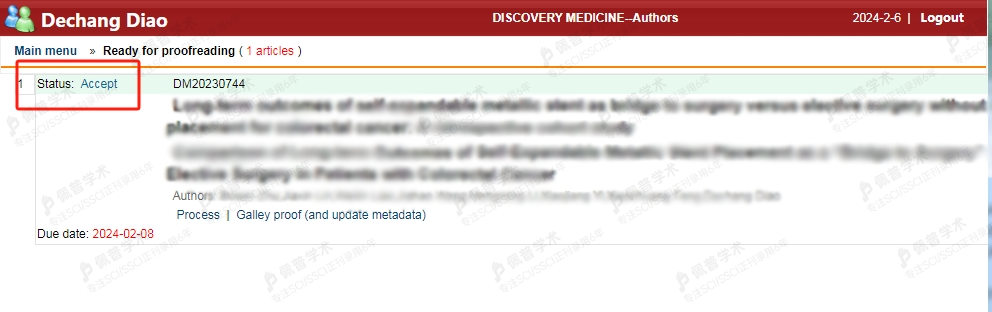

专业方向:内科学

期刊类型: SCI

影响因子:1.5

中科院分区:4

用户昵称:乐以李

职业:科研工作者

用户评价

快!准!狠!下次还找他们协助

接收函展示